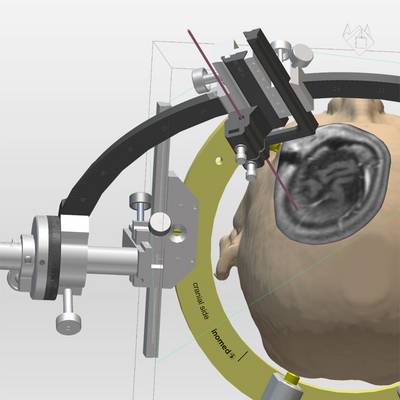

Die Möglichkeit einer schnellen Generierung von 3D Ansichten des Patientenschädels hilft bei der Verifikation der Zielpunktplanung im Zuge der THS. Durch Projektion des verwendeten Stereotaxie-Systems bekommt der Anwender eine realistische Darstellung über Anordnung und Auswirkung der Trajektorie-Planung auf den Systemaufbau.

Das Generieren von Volumen gestattet die Visualisierung von Strukturen, deren Bedeutung für die Zielpunktverifikation bei der THS groß ist. Ob nun Bild für Bild die gewünschte Struktur markiert oder per Softwarefunktion anhand von Schwellwerten automatisch erkannt wird, schlussendlich kann jedes Volumina als Objekt in der 3D-Visualisierung dargestellt werden.

Viele weitere Funktionen vervollständigen das iPS, wie das Messen von Distanzen, Winkeln und Flächen. Für die Verifikation der Trajektorie können die Bilder auf alle typischen Schnittebenen (Sagittal, Coronal, Axial) ausgerichtet werden und zusätzlich entsprechend der Draufsicht der Trajektorie (Perpendicular oder Probe´s eye) oder entlang der Trajektorie eingestellt werden.